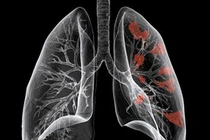

Ung thư phổi không có biểu hiện rõ rệt ở giai đoạn đầu. Khoảng 40% số người mắc bệnh chỉ được chẩn đoán khi khối u đã phát triển, và 1/3 số đó ung thư đã đến giai đoạn 3.

Nếu nhiễm trùng đường hô hấp hay cảm lạnh, cơn ho sẽ biến mất sau 1-2 tuần. Nhưng cơn ho dai dẳng, dù là ho khan hay có đờm, cũng có thể là dấu hiệu của ung thư phổi. Hãy đến khám bác sĩ ngay để được chụp X-quang và làm các xét nghiệm cần thiết khác.

Hãy chú ý đến bất kỳ thay đổi nào của cơn ho mãn tính, đặc biệt nếu bạn hút thuốc. Khi ho liên tục, ho sâu, ho khan, nhiều đờm hơn bình thường hay ho ra máu, bạn nên sắp xếp cuộc hẹn với bác sĩ.

Không nên bỏ qua dấu hiệu khó thở - xảy ra khi bạn leo cầu thang, mang vác nặng. Triệu chứng này có thể do khối u phát triển chèn lên đường hô hấp, hoặc do chất lỏng từ khối u tích tụ trong ngực.

Ung thư phổi gây ra các cơn đau ở ngực, vai, lưng. Khi ung thư phổi gây đau ngực, khó chịu có thể là kết quả của các hạch bạch huyết mở rộng hoặc di căn đến lồng ngực, màng phổi (xung quanh phổi), hoặc các xương sườn.

Thở khò khè do nhiều nguyên nhân, một trong số đó là lành tính và dễ dàng điều trị. Tuy nhiên, thở khò khè cũng là một triệu chứng ung thư phổi. Đừng chủ quan cho rằng đó là bệnh hen suyễn hoặc dị ứng. Chỉ có bác sĩ mới chẩn đoán chính xác được nguyên nhân gây ra nó.

Khàn tiếng do cảm lạnh sẽ rất đơn giản, nhưng triệu chứng này trở nên đáng lo ngại khi nó kéo dài hơn hai tuần. Khàn tiếng do ung thư phổi có thể xảy ra khi khối u ảnh hưởng đến các dây thần kinh điều khiển thanh quản và giọng nói.

Nếu bạn sút cân nhiều không rõ lý do, đó có thể là dấu hiệu của ung thư. Điều này xảy ra do các khối u phát triển nhờ sử dụng năng lượng cơ thể.

Ung thư phổi di căn đến xương sẽ gây ra các cơn đau ở lưng hoặc các khu vực khác của cơ thể. Cơn đau này sẽ trầm trọng thêm vào ban đêm khi bạn nằm nghỉ ngơi.

Nhức đầu có thể là dấu hiệu cho thấy ung thư phổi đã di căn lên não. Tuy nhiên, không phải tất cả cơn đau đầu ở người bị ung thư phổi có liên quan đến di căn não. Đôi khi, một khối u phổi tạo ra áp lực lên tĩnh mạch chủ trên, đó là tĩnh mạch lớn giúp di chuyển máu từ phần trên cơ thể đến trái tim. Áp lực này cũng có thể gây đau đầu.